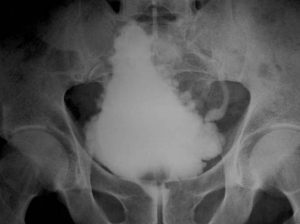

- Imaging (CT-Scan, X-Ray to diagnose your condition)